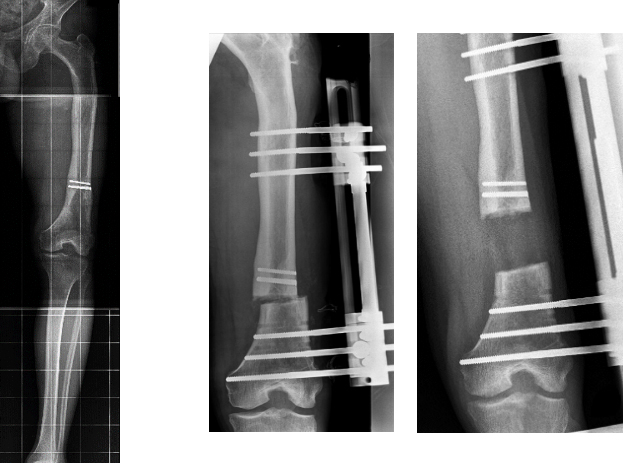

Bei der zweiten Technik kann auch nach Wachstumsabschluß das kürzere Bein verlängert werden. Dazu wird der Knochen durchtrennt und mittels eines von außen an den Knochen angebrachten Apparates der durchtrennte Knochen in die Länge gezogen. Die Verlängerungszeit beträgt 1 Milimeter pro Tag. Nach Erreichen der gewünschten Länge muß der Apparat noch belassen werden, bis der Knochen ausgehärtet ist. In der gesamten Zeit ist der Patient durch den außen anliegenden Apparat erheblich in der Bewegungsfreiheit reduziert. Der Vorteil dieser Methode liegt darin, daß eine Korrektur auf den Milimeter genau möglich ist. Es können dabei auch Korrekturen in einer anderen Ebene (Valgus, Varus, Extension, Flexion) korrigiert werden.

Bild vor und nach der Anlage des Fixateurs als auch nach Erreichen der Verlängerunsstrecke